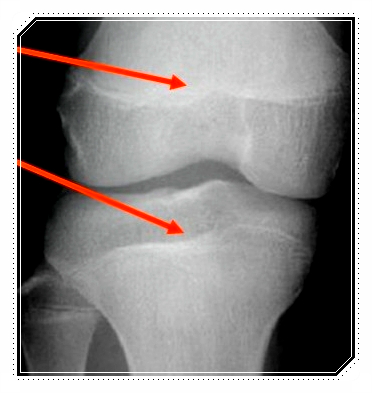

발 아치는 걸을 때 충격을 흡수하고 발목·무릎·골반까지 이어지는 힘의 전달을 조절하는 구조입니다.

즉, 몸 전체를 지탱하는 작은 기둥 같은 역할을 하고 있죠.

그래서 아치가 무너지면 걸음이 달라지고 그 영향이 위쪽으로 차곡차곡 전달될 수 있습니다.